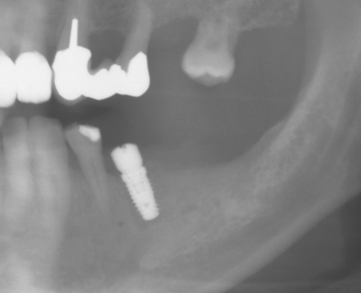

Fig 1. Implant planning and mandibular canal indicated in CBCT.

Figure 1

Patient 1 was a 69-year-old man who was a former professional athlete. He developed heart issues, which led to the use of various medications, such as metoprolol, Ventolin, Seretide, pantoprazole, Rhinocort, and Eliquis. Based on a CBCT scan (Figure 1), the patient needed augmentation in the mandibular left jaw (Siebert class I). Radiographic examination revealed a periapical lesion present at site No. 20 as well as a very thin ridge width of only 3.7 mm in the posterior mandible. Implant planning was performed using planning software, and a custom-made titanium mesh was designed (Figure 2).12